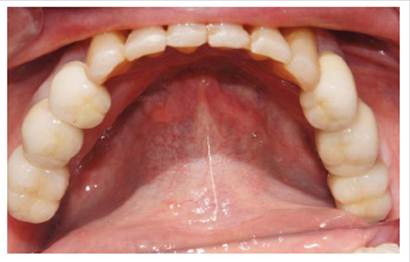

Luego se procedió a la fabricación de la estructura metálica del maxilar superior con la ayuda de una pantalla de silicona obtenida del protocolo reverso, esta estructura presentó un asentamiento pasivo comprobado clínica y radiográficamente luego de realizar los cortes y soldajes necesarios (Figura 5). Se realizó el enfilado para la prótesis híbrida con dientes Ivostar/Gnathostar donde se evaluó estética y fonación. En el maxilar inferior se torquearon los pilares CM recto para la pieza 35 y Pilares angulados (17°) a nivel de piezas 36 y 46 fresados con la ayuda de una guía de colocación de pilares (Figura 6) y se fabricaron coronas de metal cerámica. Para finalizar se procede a la instalación de la prótesis híbrida superior, la cementación de las coronas con cemento temporal y la instalación de una férula de DCM (figura a y b). Finalizado el tratamiento se realizaron controles periodontales y protésicos periódicos donde se comprobó la correcta concientización del paciente en cuanto a su mantenimiento. (Figura 8)

Figura 7 a Instalación de la prótesis híbrida superior

Figura 7 b coronas cementadas sobre implantes en Max. Inferior